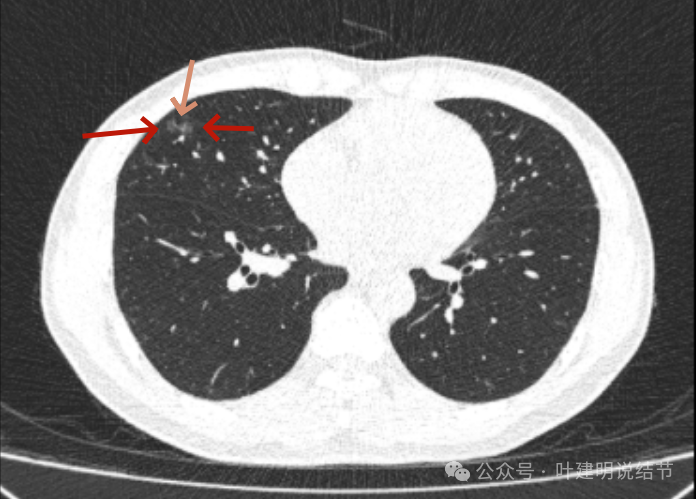

2022年11月时,病灶较前范围有所扩大,表面现分叶征,灶内有血管穿行,轮廓与边界清楚。